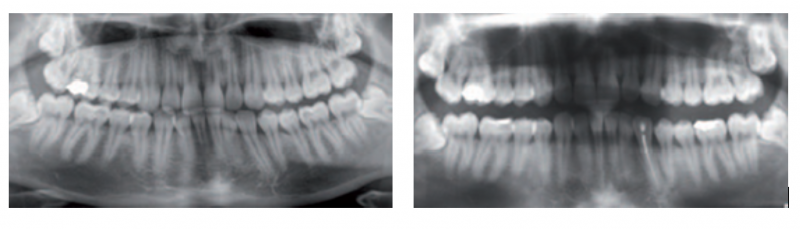

실제 사례로는 ▲치아 및 잇몸 손상 ▲부정교합 ▲턱관절 장애 ▲장치 파손 및 기도흡입 등의 위험이 보고됐다. 또 ▲치은부종 ▲점막궤양 ▲플라스틱 파편 흡입 등의 부작용을 겪은 사례가 확인됐다.

이와 관련, 황우진 대한치과의사협회 홍보이사는 “치아교정, 이갈이 방지, 코골이 방지 장치는 반드시 치과의사의 정확한 진단과 환자 맞춤형 제작을 거쳐야 하며 구강 내 장치 지속적인 모니터링과 조정이 필요하다”고 강조했다.